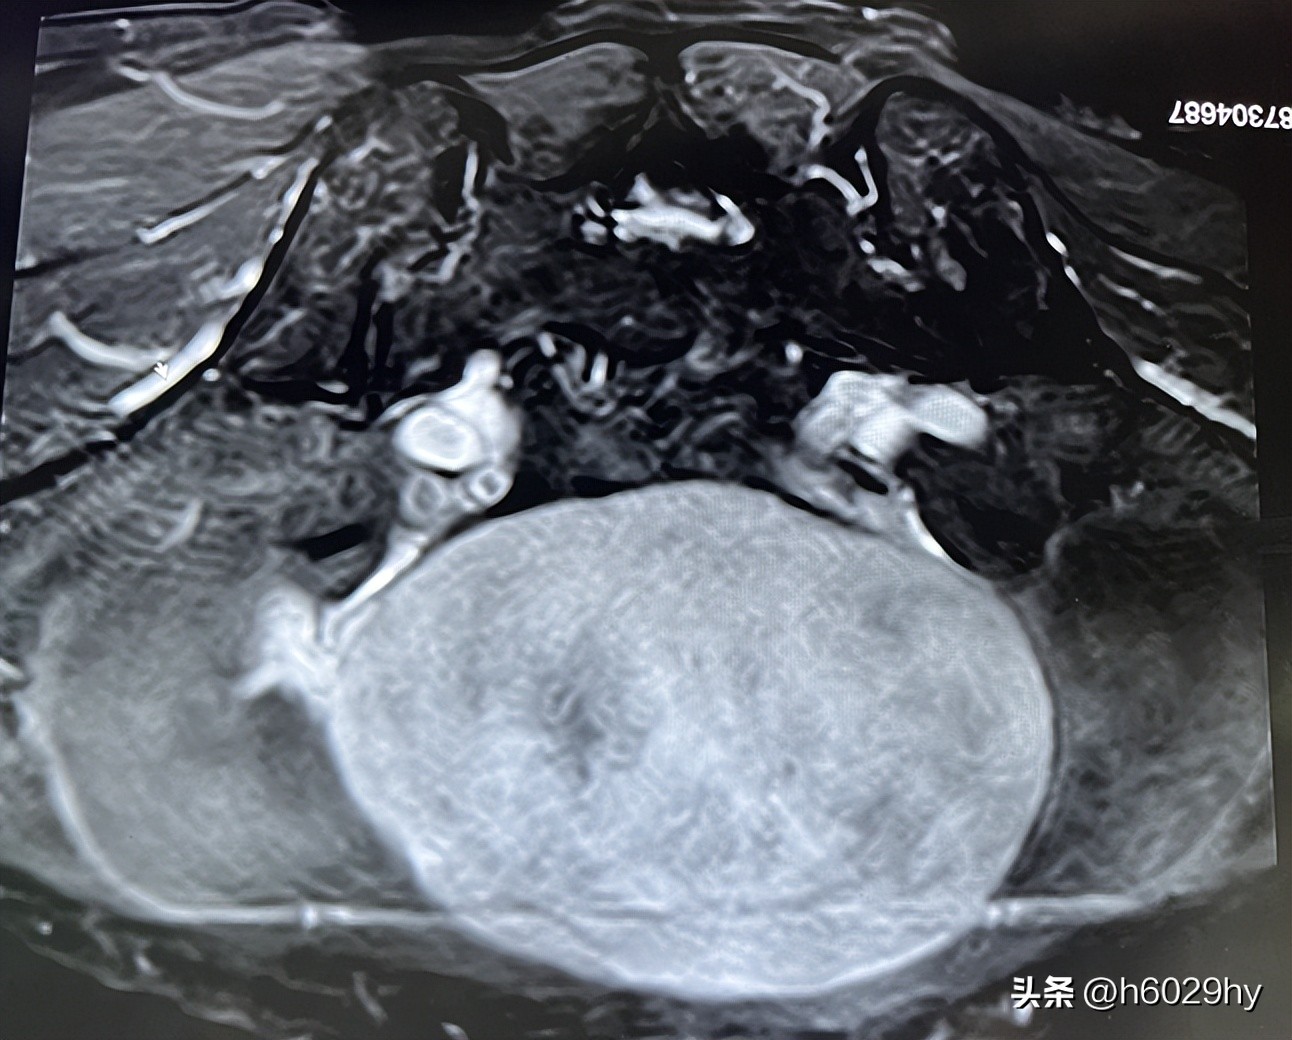

盆腔增强MRI:子宫前方巨大占位(12cm×8.4cm),考虑来源于卵巢,纤维卵泡膜细胞瘤,盆腔及腹腔大量积液。

术中见淡黄色清亮腹水约1500ml,吸取10ml腹水查脱落细胞,洗净腹水后,见盆腔内一直径约13cm的质硬包块,呈白色,表面光滑,表面见数条增生血管,来源于左侧卵巢(未见正常卵巢组织)。根据术中探查情况及术前谈话,拟行双侧附件(卵巢+输卵管)切除术。手术顺利,术后病理检查提示左侧卵巢富于细胞的纤维瘤;右侧卵巢组织,双侧输卵管组织。术后,患者恢复良好。